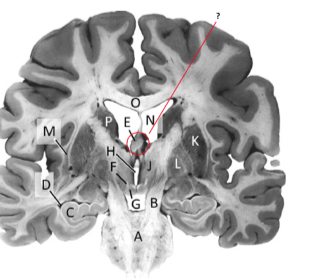

Name this and state its function.

Corpus Callosum.

Name and state its function.

Lateral ventricles.

Hippocampus.

Thalamus.

Third ventricle.

Caudate nucleus.

Name this ,state its function and the name of the structures closely associated with it.

Putamen.

Name this, state its function and its components[4 marks].

Globus Pallidus.

Components:

Crus Cerebri.

Name this and state its function. Also, state all 3 fibres involved.

Basilar pons.

Claustrum.

Name.

Temporal horn of lateral ventricle.

Name this, state its function and consequence of lesion in this area.

Fornix.

Transmits Theta waves aswell.

Lesion: anterograde amnesia.

Name this and state its function. And what tract is involved?

Mamillary bodies.